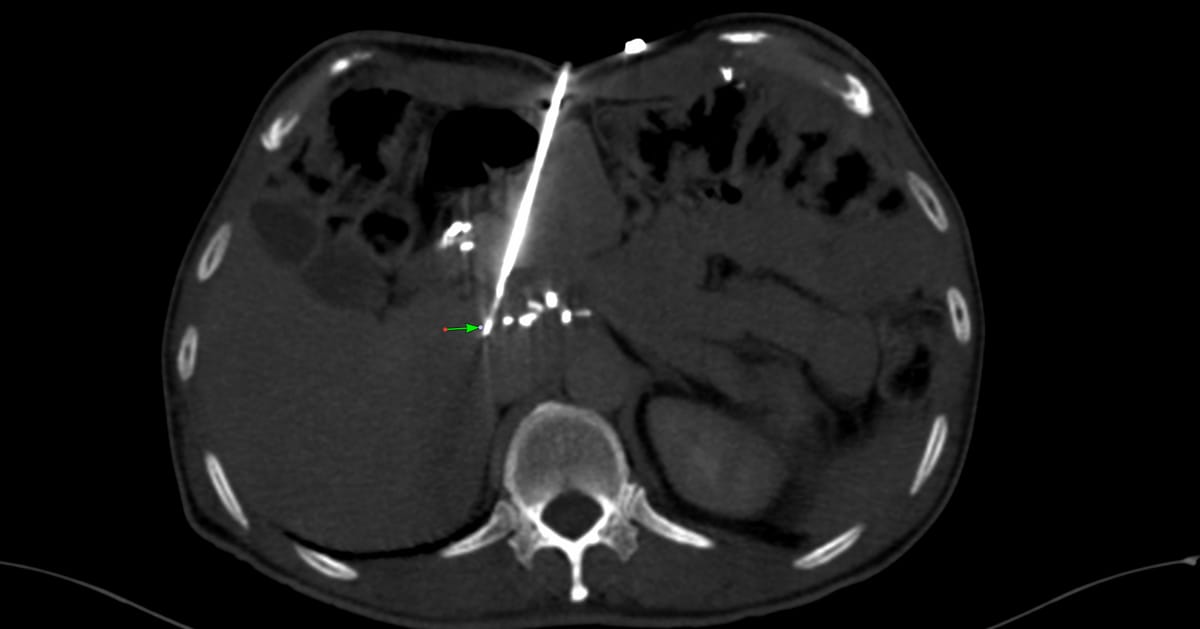

63-years old, CKD on dialysis for 4 years developed bilateral chylothoraces 3 months ago and was referred for a CT lymphangiogram (CTL)

While there are different ways of doing lymphangiograms, a relatively new technique is CTL with intranodal injection of non-ionic iodinated contrast and rapid scanning within 2-5 minutes.

The video explains what I did - injecting a retroperitoneal node in the prone position instead of an inguinal node with a successful CTL showing lymphatic duct obstruction at the D5-6 level.

The paradigm has changed. This procedure is now simple and can be performed by anyone who can put a needle into a node proximal to the site of obstruction with intranodal injectino of regular non-ionic iodinated contrast.